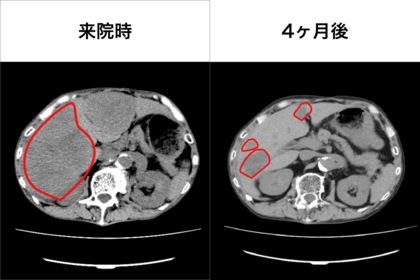

クリニック5か条を習慣化させた患者IさんのCT腹部画像

Iさんは73歳の男性。来院時、進行胃がん、多発肝転移、がん性腹膜炎(腹水)、両下肢浮腫があった。このままなら余命3か月、抗がん剤治療をすれば6か月から1年という診断だった

4ヶ月後の画像を見ると…

週1~2回の点滴(栄養剤、若干のステロイドなど)を行うとともに、「5か条」だけを習慣化したところ、肝臓の約9割を占めていた腫瘍が縮小していた